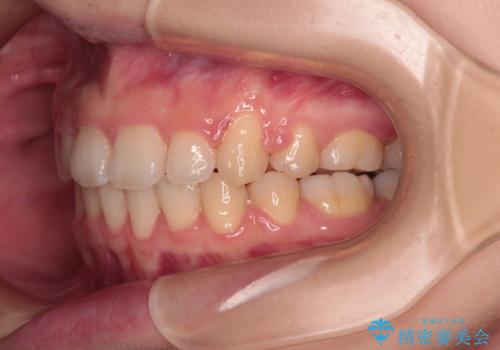

- 上下の前歯が突出しており、口が閉じにくいとのことで来院された患者様です。

上下前歯が著しく前突している状態であったので、上下左右の第1小臼歯4本を抜歯し、ワイヤー装置にて矯正治療を行うこととしました。

舌の突出癖により、前突になったと考えられたため、舌のトレーニングをしっかりと行うよう指導しました。